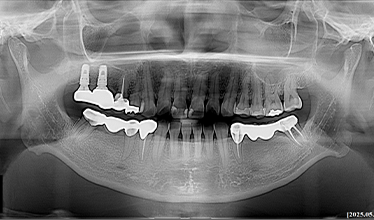

CASE 01

-

임플란트 식립 전 -

임플란트 식립 후 -

임플란트 보철 후